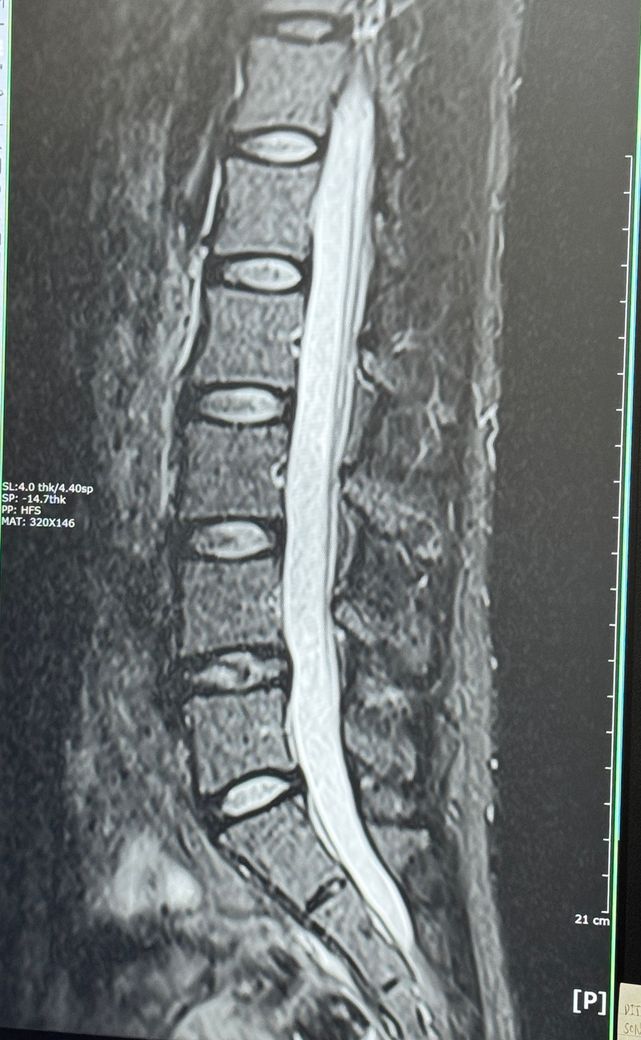

의사쌤 말로는 4-5번 디스크가 터졌다고 하나 수술할 정도나 걱정할 정도는 아니고 그냥 쉬면 된다 하는데 생각보다 방사통이 심합니다..

왼쪽만 이랬는데 이래저래 오른쪽까지 지금 허벅지 앞쪽 뒷쪽 엉덩이 종아리까지 찌릿 하네요..

• 3번 째 사진